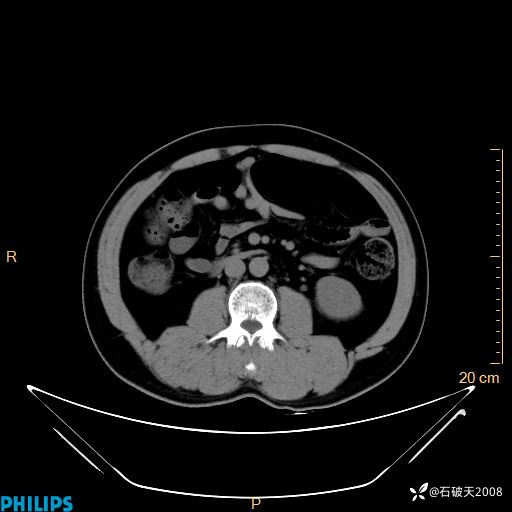

平扫轴位